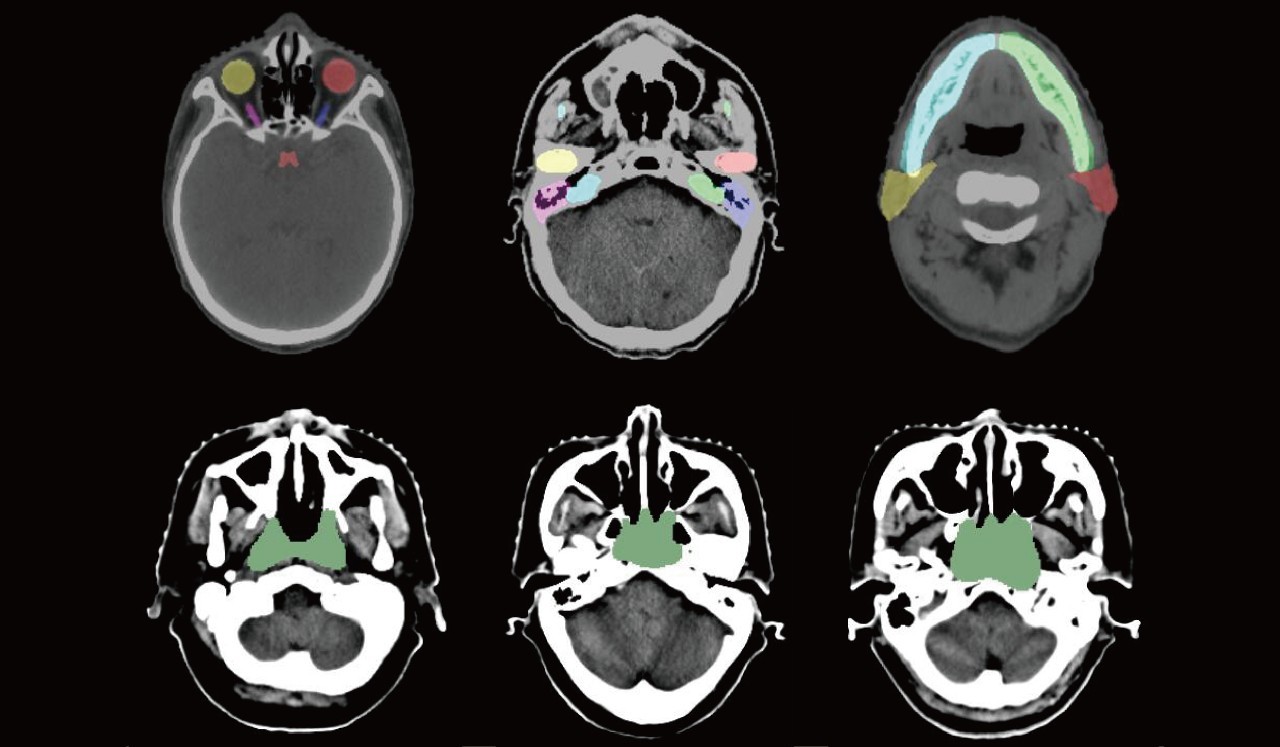

醫(yī)生在為病人制定放療規(guī)劃的實(shí)際過程中,需要在病人拍攝的幾十甚至上百?gòu)圕T圖像上進(jìn)行危及器官和靶區(qū)勾畫,這個(gè)過程占據(jù)了放療醫(yī)生大量時(shí)間和精力,而自動(dòng)危及器官及靶區(qū)勾畫算法能夠極大地降低放療規(guī)劃時(shí)間,提升醫(yī)生效率的同時(shí)降低放療整體成本。

此次公布數(shù)據(jù)集將包括大規(guī)模的放療模擬定位CT數(shù)據(jù)以及放療專家標(biāo)注的結(jié)構(gòu)和腫瘤靶區(qū)(GTV),用于“頭頸部危及器官(OAR)分割”、“胸部危及器官(OAR)分割”、“鼻咽癌放療靶區(qū)(GTV)分割”和“肺癌放療靶區(qū)(GTV)分割”四項(xiàng)挑戰(zhàn)任務(wù)。

本次數(shù)據(jù)集規(guī)模比以往所有公開數(shù)據(jù)集規(guī)模都大,它們包含了50位鼻咽癌患者的CT數(shù)據(jù)及相應(yīng)的1100個(gè)危及器官和放療靶區(qū)GTV的標(biāo)注,50位肺癌患者的CT數(shù)據(jù)及相應(yīng)的300個(gè)危及器官和放療靶區(qū)GTV的標(biāo)注,這些數(shù)據(jù)集的釋放,將極大地推動(dòng)CT圖像中危及器官和靶區(qū)勾畫研究的進(jìn)展。